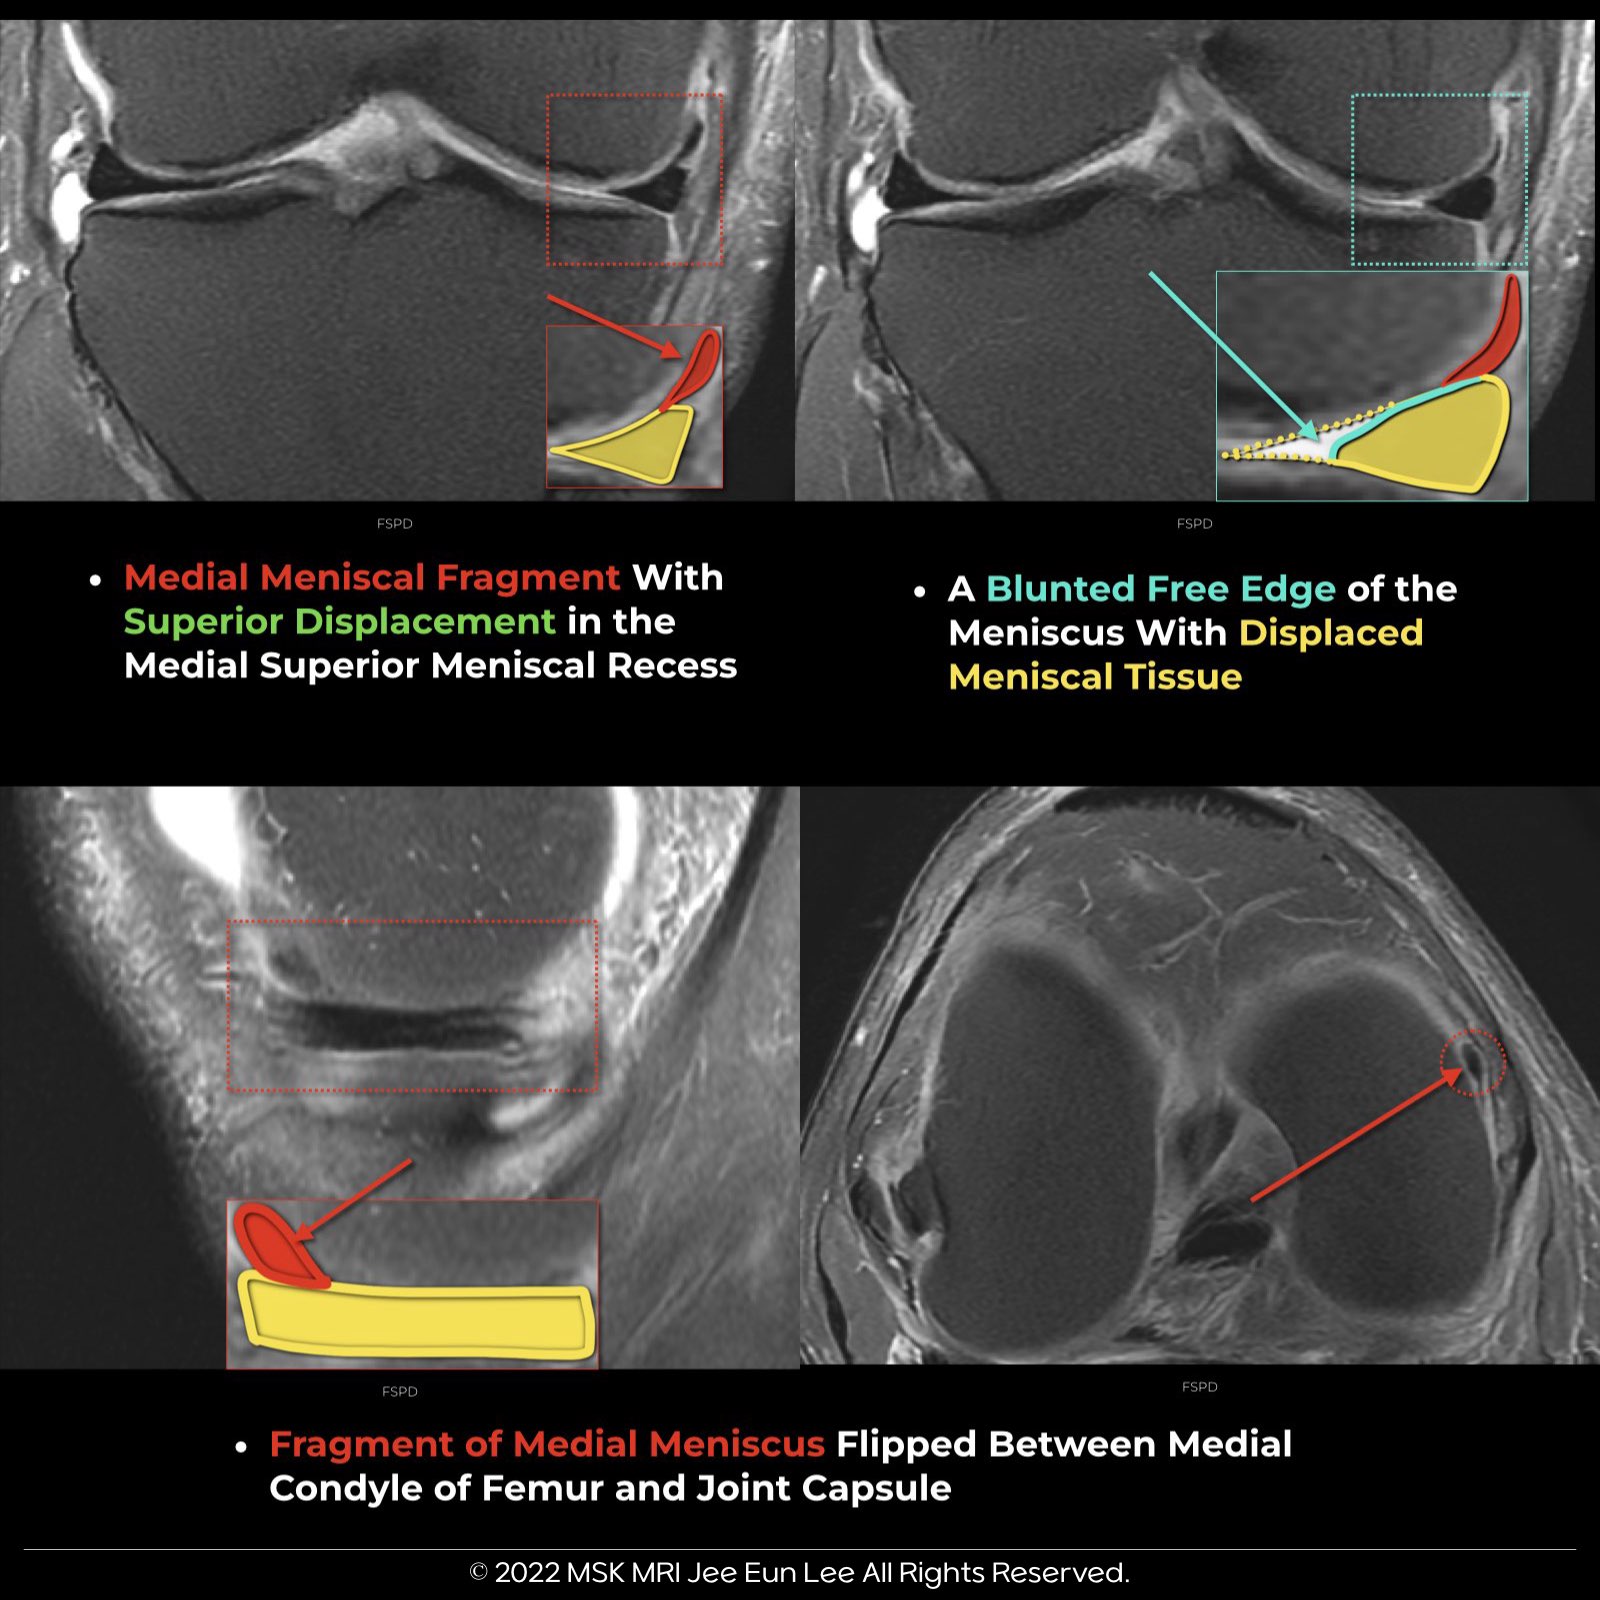

- For medial meniscus tears, 93% of fragments are located medially or posterolaterally, commonly in the superior or inferior recesses.

- The remaining cases often have the fragment in the medial gutter's recesses, predominantly the superior recess.